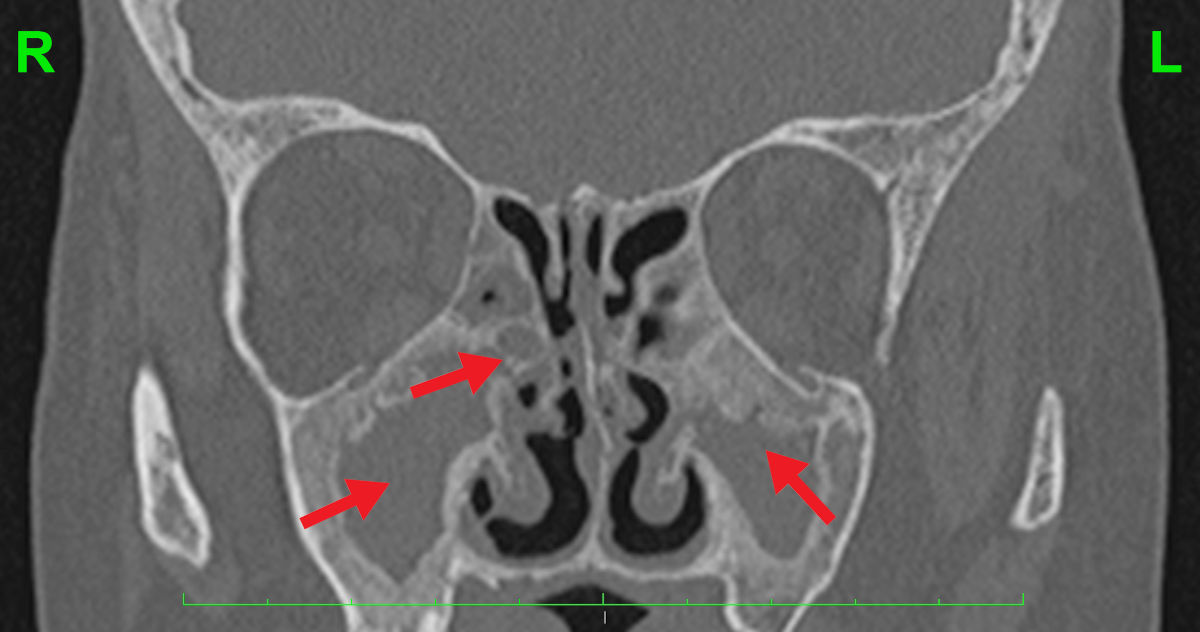

CT and MRI scans showed no aeration of the paranasal sinuses, foci of bone destruction and a significant amount of scar tissue. The anatomy of the nasal cavity was completely disturbed (Fig. 4-5).

Figure 5. Coronal CT scan shows no aeration of the paranasal sinuses and deformation of the nasal cavity anatomy.